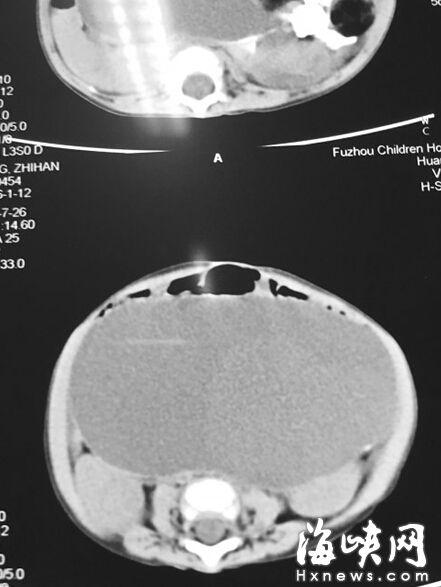

CT顯示,小云腹腔被畸胎瘤霸占

7月22日,家人抱著小云到福州兒童醫(yī)院,福州兒童醫(yī)院副院長、小兒外科學(xué)博士林芃一摸她肚子,推斷可能是巨結(jié)腸或腫瘤。果然,B超結(jié)果顯示,小云 的左側(cè)腹膜后藏著一個(gè)巨大腫瘤,被腸管擋住了,為此多次漏診。腫瘤直徑約20厘米,幾乎霸占整個(gè)腹腔。7月29日,醫(yī)生花了3個(gè)小時(shí)剝離腫瘤,其皮質(zhì)硬。 醫(yī)生將瘤中的液體吸出500多毫升,“排球”癟了1/3,才被順利取出。這是一個(gè)畸胎瘤,足有2斤重,這么大的很罕見。但畸胎瘤分化不成熟,沒有成形的毛 發(fā)、牙齒等組織,很可能是惡性腫瘤,目前還在等病理報(bào)告。